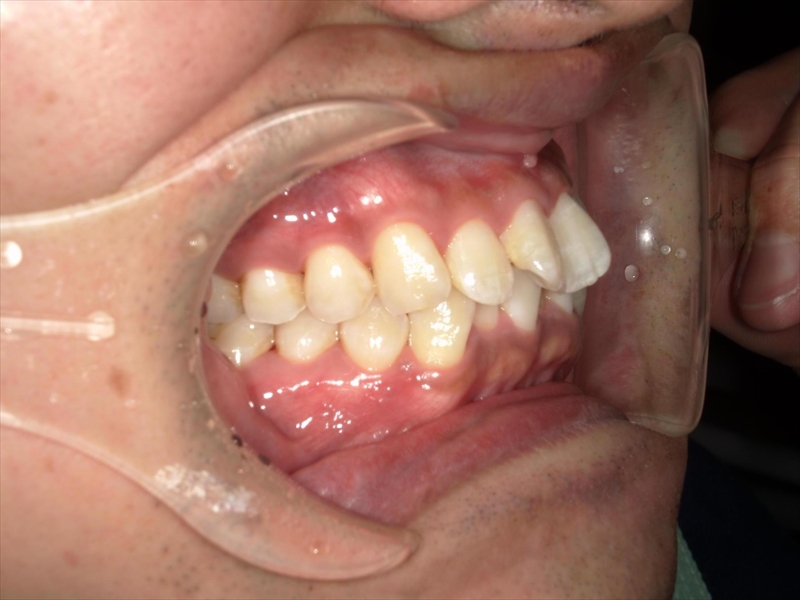

- 上あごの前歯がV字状の出っ歯

- 上あごに対して下あごがかなり小さい(過蓋咬合)

前歯のねじれ(V字)と出っ歯を下げるスペースを確保のため、両側1~5番目を0.2~0.5ミリ(計4ミリ)削ることと、奥歯から順に奥へ下げながら外側へ広げる計画を立案しました。